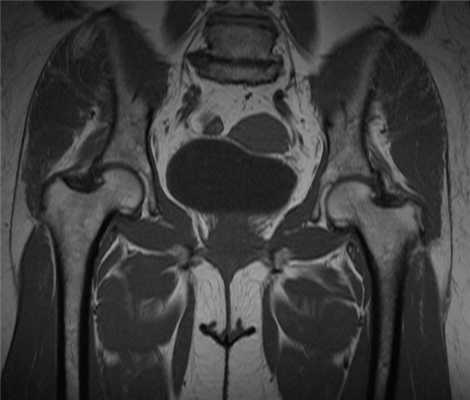

Импиджмент синдром на МР-фото

К механическому конфликту между бедренной головкой/шейкой и краем вертлужной впадины приводят одно- или двусторонние дефекты костей врожденного или приобретенного генеза. Видоизмененные компоненты сочленения вызывают дисфункцию конечности за счет соударения во время движения. Патологическое трение костей способствует разрастанию остеофитов на фоне постоянной травматизации вертлужной губы. Если своевременно не диагностировать заболевание и не начать лечение, последняя с течением времени разорвется., Хрящевая ткань сочленяющих костей будет разрушена. Подобный механический конфликт часто способствует формированию коксартроза и сопровождается прогрессирующим болевым синдромом.